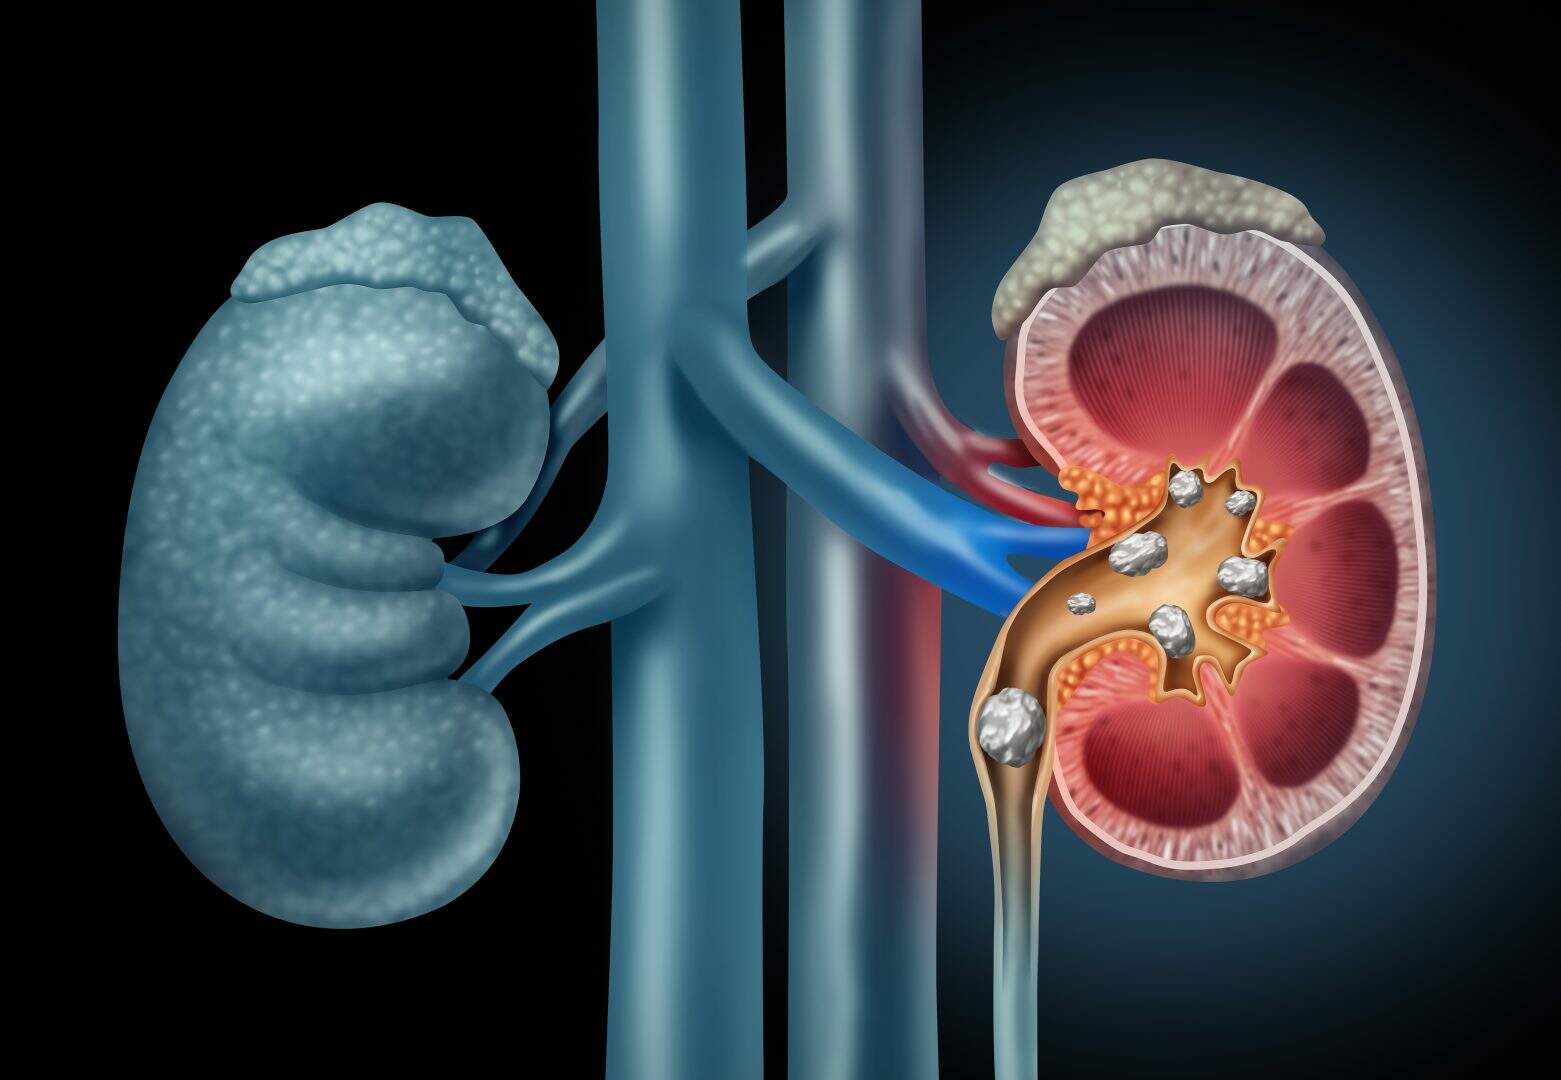

As pedras nos rins são formações sólidas de sais minerais e uma série de outras substâncias que podem migrar pelas vias urinárias.

Foto: Reprodução

As pedras são formações sólidas de sais minerais e uma série de outras substâncias que podem migrar pelas vias urinárias. Os cálculos têm variados tamanhos, provocando obstrução parcial ou total do fluxo da urina. A dor começa nas costas e se irradia para o abdômen em direção à região inguinal. Há picos de cólica intensa seguida de certo alívio. As crises podem ser acompanhadas por náuseas e vômitos, necessitando de atendimento de urgência. A falta de tratamento pode trazer complicações, entre elas: novos cálculos, infecção urinária de repetição e até a perda da função renal. O urologista lembra que já realizou um estudo no Hospital Santa Marcelina (SP) que revelou um dado alarmante: 75% das pessoas que perderam um rim por causa benigna tiveram infecção crônica por cálculo obstrutivo no ureter ou rins.